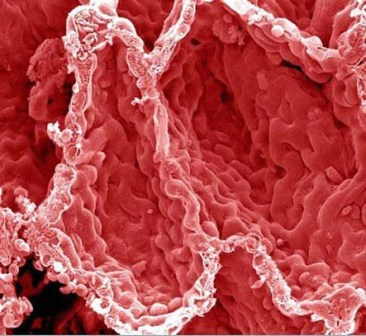

سرخرگ